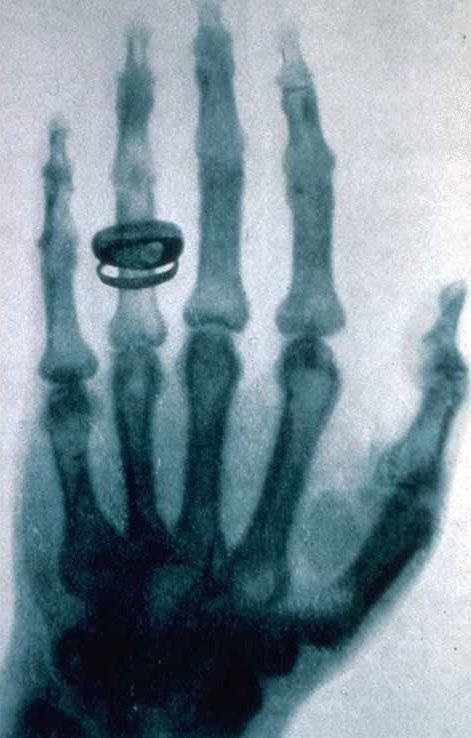

9. Razele X

Prima imagine cu raze X prezintă mâna unei femei cu o vereghetă pe deget. Fizicianul Wilhelm Rontgen a creat imaginea mâinii soţiei sale în 1895, aceasta a declarat ,,Mi-am văzut moartea”.